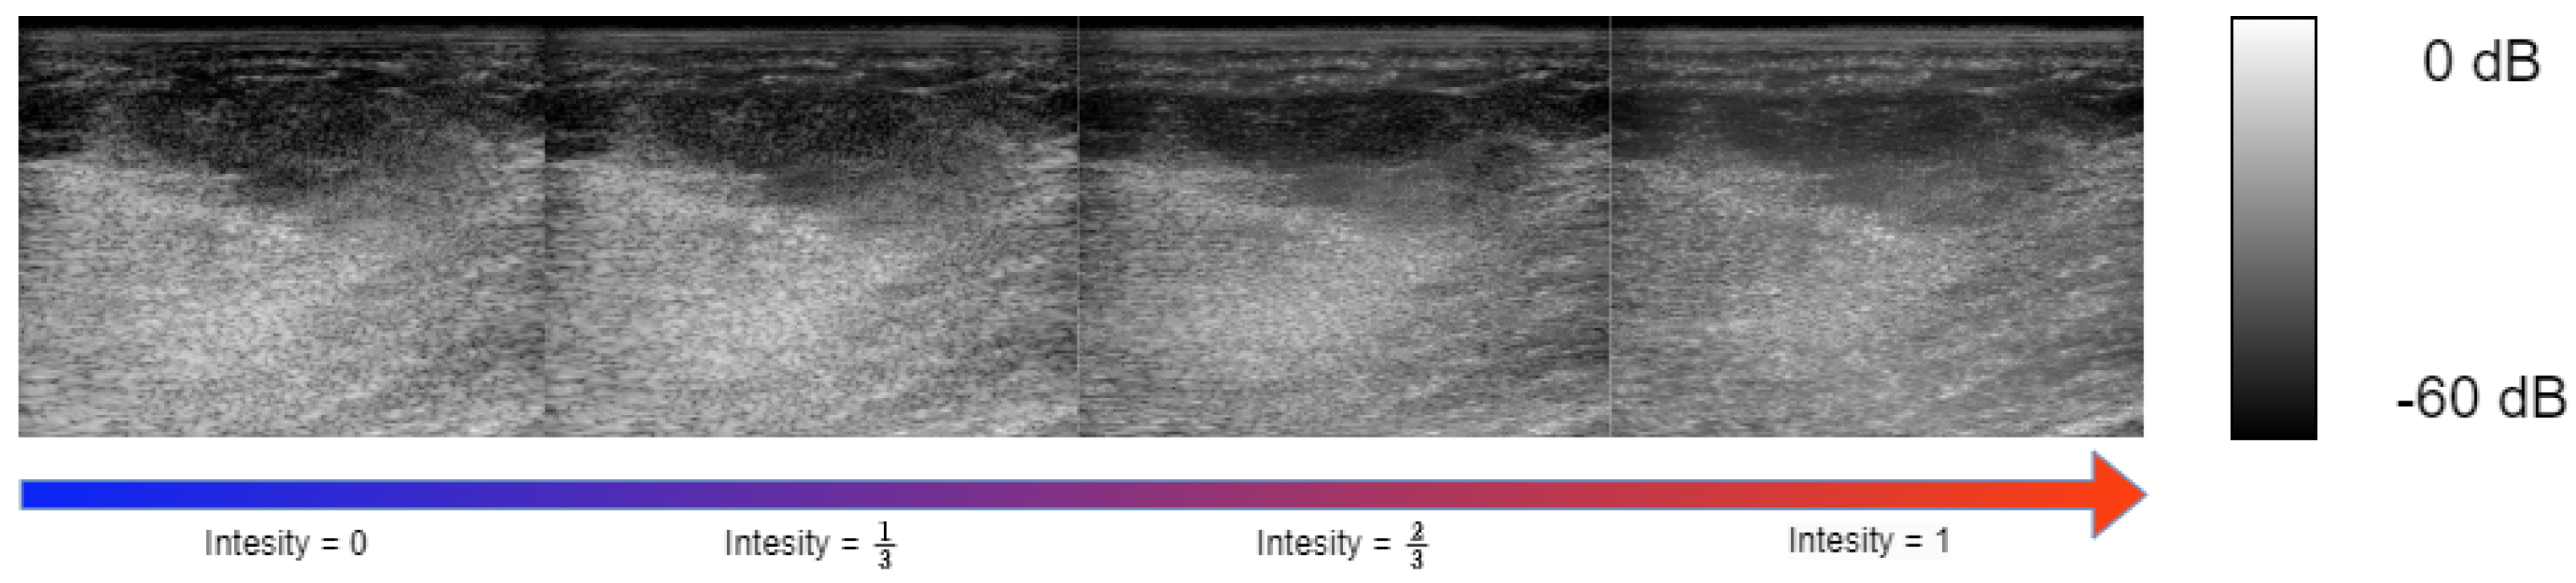

4.3. Controlling Task Intensity